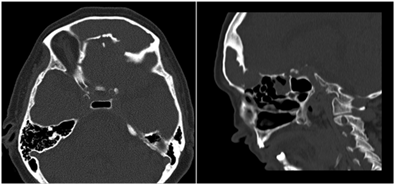

Se le solicita una tomografía de nariz y senos paranasales donde encontramos el velamiento total de ambos senos frontales, ocupados por densidad de partes blandas, adelgazamiento, erosión y destrucción de las paredes superior, posterior e inferior del seno frontal izquierdo con invasión de órbita izquierda y desplazamiento ocular hacia abajo y afuera (Figura 2), también se solicita una resonancia magnética contrastada constatándose la ocupación de ambas digitaciones del seno frontal por gran mucocele, que no restringe a la difusión y muestra tenue realce periférico; con remodelado óseo y efecto de masa sobre las estructuras adyacentes, en especial sobre el globo ocular izquierdo generando proptosis, realce meníngeo laminar regional a nivel del aspecto frontal izquierdo, sin edema parenquimatoso ni focos de abscesos y nervios ópticos de espesor y contornos conservados, sin realce patológico (Figura 3).

Lo que se espera encontrar con las técnicas de diagnóstico imagenológico son, con la tomografía, un adelgazamiento, erosión e incluso destrucción de las paredes óseas, principalmente la pared posterior debido a su delgadez, poniendo en comunicación las estructuras adyacentes con el seno afecto, el cual se encuentra ocupado por una densidad de partes blandas, homogénea sin aire que no realza con el contraste. La resonancia magnética nos sirve para diferenciarlos de los tumores nasosinusales y delimitar el contacto con estructuras adyacentes, los hallazgos en T1 encontramos una masa de contenido hipointenso con una delgada línea periférica hiperintensa. Todos estos hallazgos coinciden con los hallazgos imagenológicos del caso presentado8-10.